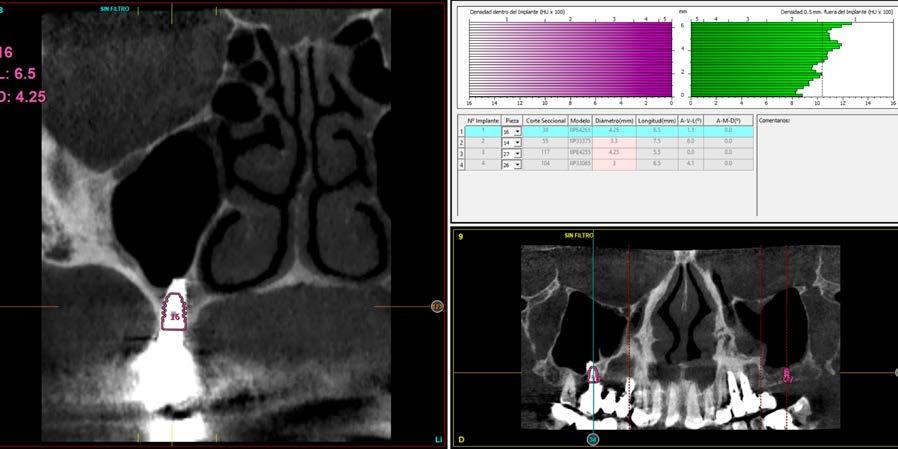

Issuu converts static files into: digital portfolios, online yearbooks, online catalogs, digital photo albums and more. Sign up and create your flipbook.